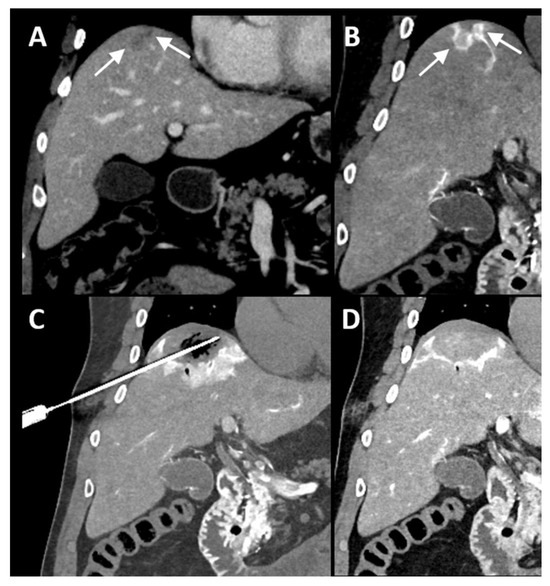

| Case No. | Tumor Size (mm) | Catheter Tip Position | Amount and Type of Contrast per Injection | Ablation Device | Institute |

|---|---|---|---|---|---|

| 1 | 20 mm | Common hepatic artery | 15–20 mL Visipaque™ | Emprint™ Microwave Ablation System, Medtronic-Covidien, Boulder, CO, USA | MD Anderson, Houston, TX, USA |

| 2 | 20 and 7 mm | Common hepatic artery | 4 mL Xenetix 300® | Cool-tip™ RFA Ablation Aystem, Medtronic-Covidien, Boulder, CO, USA | Gustave Roussy, Villejuif, France |

| 3 | 12 mm | Left-sided hepatic artery | Not specified | Cool-tip™ RFA Ablation System | Gustave Roussy |

| 4 | 9 mm | Common hepatic artery | 10 mL Xenetix 300® | Emprint™ Microwave Ablation System | Amsterdam UMC, Amsterdam, The Netherlands |

| 5 | 15 mm | Coeliac trunk | 20 mL Xenetix 300® | Emprint™ Microwave Ablation System | Amsterdam UMC |

| 6 | Not applicable | Common hepatic artery | 20 mL Xenetix 300® | Emprint™ Microwave Ablation System | Amsterdam UMC |

| 7 | Confluent | Common hepatic artery | 10 mL Xenetix 300® | NanoKnife system under ECG-gating; AccuSync model 72, AngioDynamics, Latham, NY, USA | Amsterdam UMC |

| 8 | 15 mm | Common hepatic artery | 15–20 mL Visipaque™ | Emprint™ Microwave Ablation System | MD Anderson |